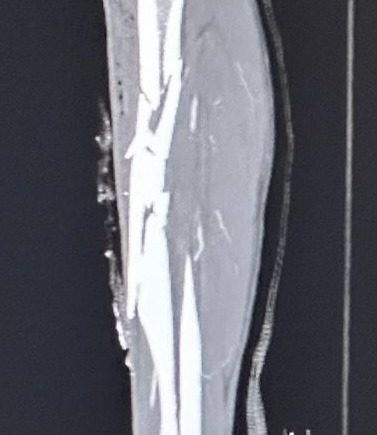

On June 12, 2025, I suffered a devastating accident during my usual after work visit to South Fork river. A 4,000 pound boulder rolled over my leg, crushing my tibia and fibula and nearly severing my lower leg. Alone and with no cell service, I had to fight for my life, crawling, climbing, and driving myself miles in excruciating pain to find help. I made it to cell signal and reached my long time best-friend and co-parent, Kim Latos. She happened to be close by and arrived to find me in a puddle of blood and slipping into unconsciousness. I had lost over half my blood once we arrived at the ER.

I was airlifted to Redding Mercy Medical Trauma Center for emergency surgery, where a titanium rod was inserted to save my leg. Days later, I was hospitalized again with a severe, antibiotic-resistant form of pneumonia I contracted during surgery, bringing me close to death for the second time in two weeks.